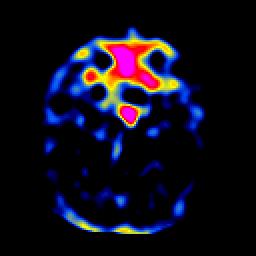

SPECT TL Study #1 -- Slice #17

[Home][Help][Clinical][Tour 1][Tour 2][Tour 3] Slice 17